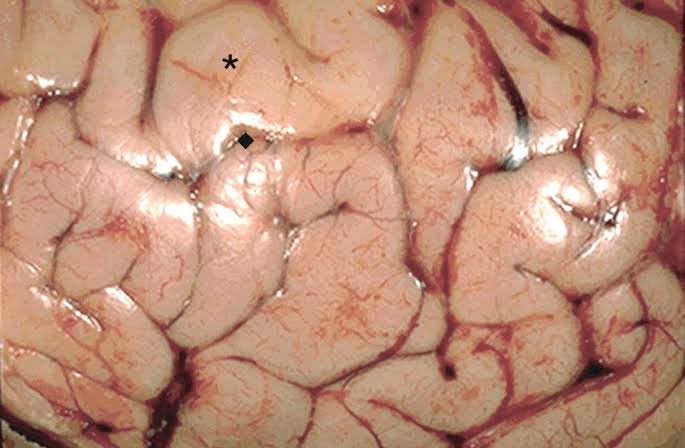

To start, the gorilla brain looks a dying human brain with massive cerebral edema and is flat/ smooth and missing our sulci and gyri contours.